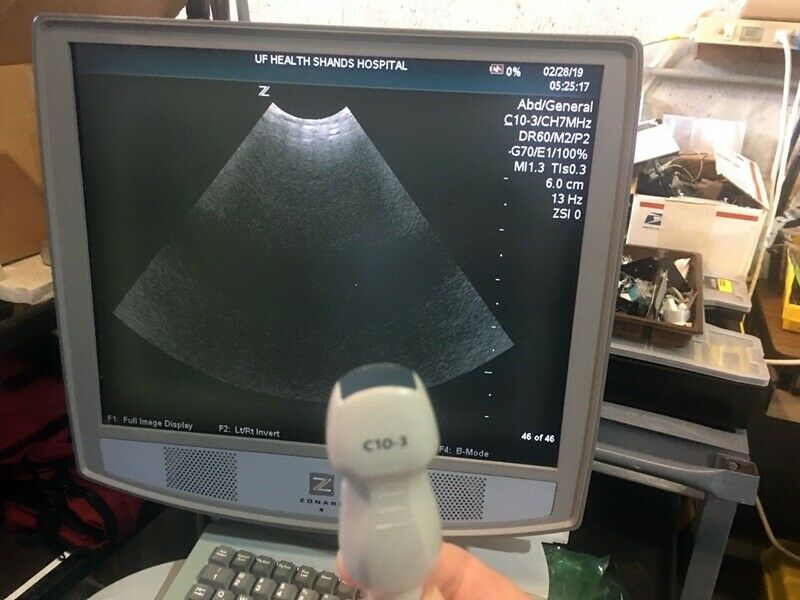

Zonare C10-3 Probe , Ultrasound Transducer

Sale price$ 1,092.24

Regular price$ 1,332.00